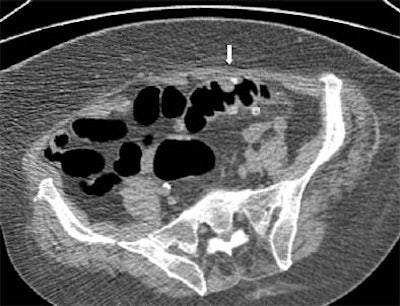

| Supine view: severe diverticulosis with global wall thickening and impacted diverticulum on the posterior aspect (white arrows). |

"Imaging findings are unequivocal when it presents as a hyperdense ring with a hypodense center on the axial images," the group wrote, adding that other researchers have reported different manifestations of impacted diverticula, such as barium or air attenuation, which did not render the findings equivocal.